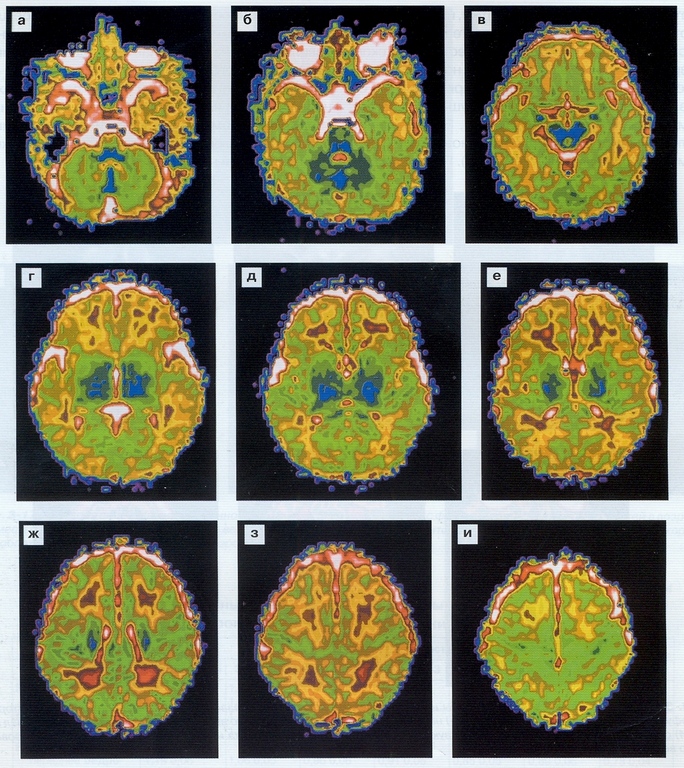

Уникальность МР спектроскопии головного мозга – возможность изучать метаболизм здоровых и патологических клеток. Основа функционирования метода – регистрация спектра от ядер атомов водорода (протонов), входящих в состав разных химических соединений.

Для изучения биохимического обмена мозговой ткани анализируются спектральные частоты соединений, концентрация и соотношение которых изменяется при патологических состояниях.

Изменение содержания веществ при разных нозологических формах специфично, что позволяет врачу с высокой степенью достоверности диагностировать заболевание.

Уникальное преимущество исследования при сравнении с другими МРТ аналогами – выявление патологического метаболизма в мозговой ткани до появления клинических симптомов болезни.

Современное технологическое новшество – мультиядерная спектроскопия – выявляет концентрацию углерода, фосфора, некоторых других химических элементов одновременно от нескольких отделов мозга на основе спектрального графика. Подход позволяет сравнивать метаболизм противоположных центров, периферических участков опухоли.

Самое частое применение протонной спектроскопии – оценка особенностей новообразований мозга, дифференциальная диагностика разных типов опухолей. Обследование не выявляет гистологический тип образования, но достоверно верифицирует рак. Измененный метаболизм злокачественных клеток характеризуется уменьшением соотношения между ацетиласпартатом и креатинином, увеличением холина, лактата.